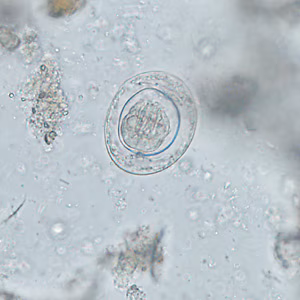

A 42-year-old man with a history of living abroad in Peru for a year returned home to the United States. He reported to his health care provider that he had been experiencing vague intermittent abdominal discomfort. A stool specimen was collected and processed for ova-and-parasite (O&P) examination. Figures A–E show what was observed at 400x magnification in moderate numbers; Figures A and B are of the same object in different focal planes. The object in Figure D is approximately 33 micrometers in diameter. What is your diagnosis? Based on what criteria?

Figure E